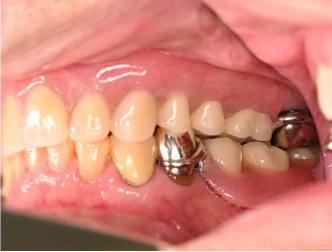

Before

▼初診時に使用していた部分入れ歯を装着したところ